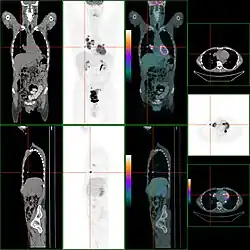

Beim PET/CT wird der Patient unmittelbar hintereinander durch beide Detektorringe (Gantries) von CT und PET gefahren. Da der CT-Datensatz für die Rekonstruktion der PET-Daten benötigt wird, wird in der Regel zunächst eine CT-Aufnahme durchgeführt und die PET-Aufnahme daran angeschlossen. So kann bereits nach Beendigung der Aufnahme der ersten Bettposition mit der Bildrekonstruktion begonnen werden. Würde zunächst der PET-Datensatz aufgenommen, müsste mit dem Beginn der Bildrekonstruktion der PET-Daten gewartet werden, bis der CT-Datensatz rekonstruiert ist und zu unerwünschten Verzögerungen im Arbeitsablauf führen, denn die Rekonstruktion eines Ganzkörper-PET-Datensatzes benötigt je nach Gerät und Rechenmethode ca. 10–45 Minuten Zeit. Eine laufende CT-Aufnahme ist für den Patienten daran erkennbar, dass der Tisch bewegt wird, während gleichzeitig ein Motorengeräusch hörbar ist, das in erster Linie von der Rotationsbewegung von Röhre und Detektorsystem stammt. Die Gantries sind bei einigen Systemen im selben Gehäuse untergebracht und nicht einzeln von außen sichtbar. Die errechneten Bilder werden im Computer automatisch fusioniert.

Die Befundung des PET- oder PET/CT-Bildes erfolgt durch Betrachtung der rekonstruierten Schnittbilder (axial, koronar oder sagittal). Bei PET/CT-Geräten ist die Darstellung von PET und CT verknüpft, so dass automatisch die Position des korrelierenden PET-Bildes gezeigt wird, wenn der Bildkursor im CT-Bild verschoben wird.

Für eine Übersichtsdarstellung wird ein sogenanntes MIP-Bild (Maximum Intensity Projection) herangezogen. In dieser Darstellung ist das gesamte Untersuchungsobjekt abgebildet und man erlangt einen schnellen Überblick über Regionen erhöhter Aufnahme. Zur nochmals besseren Visualisierung kann man das MIP um sich selbst rotieren lassen, um das Untersuchungsobjekt von allen Seiten zu zeigen.

Ein PET/CT-Gerät kombiniert die hohe Ortsauflösung (von bis zu 0,35 mm) und detailreiche Anatomiedarstellung des CT-Geräts mit den hochsensitiven Stoffwechselinformationen aus der PET.

Die Kombination der Modalität CT mit der Modalität PET führte dazu, dass sich die Gesamt-Aufnahmezeit drastisch verkürzte, die Bildqualität der PET-Aufnahme erheblich verbesserte und die Überlagerung der beiden Bilder im klinischen PET-Hauptanwendungsgebiet – der Onkologie – einen signifikanten diagnostischen Mehrwert bedeutete.